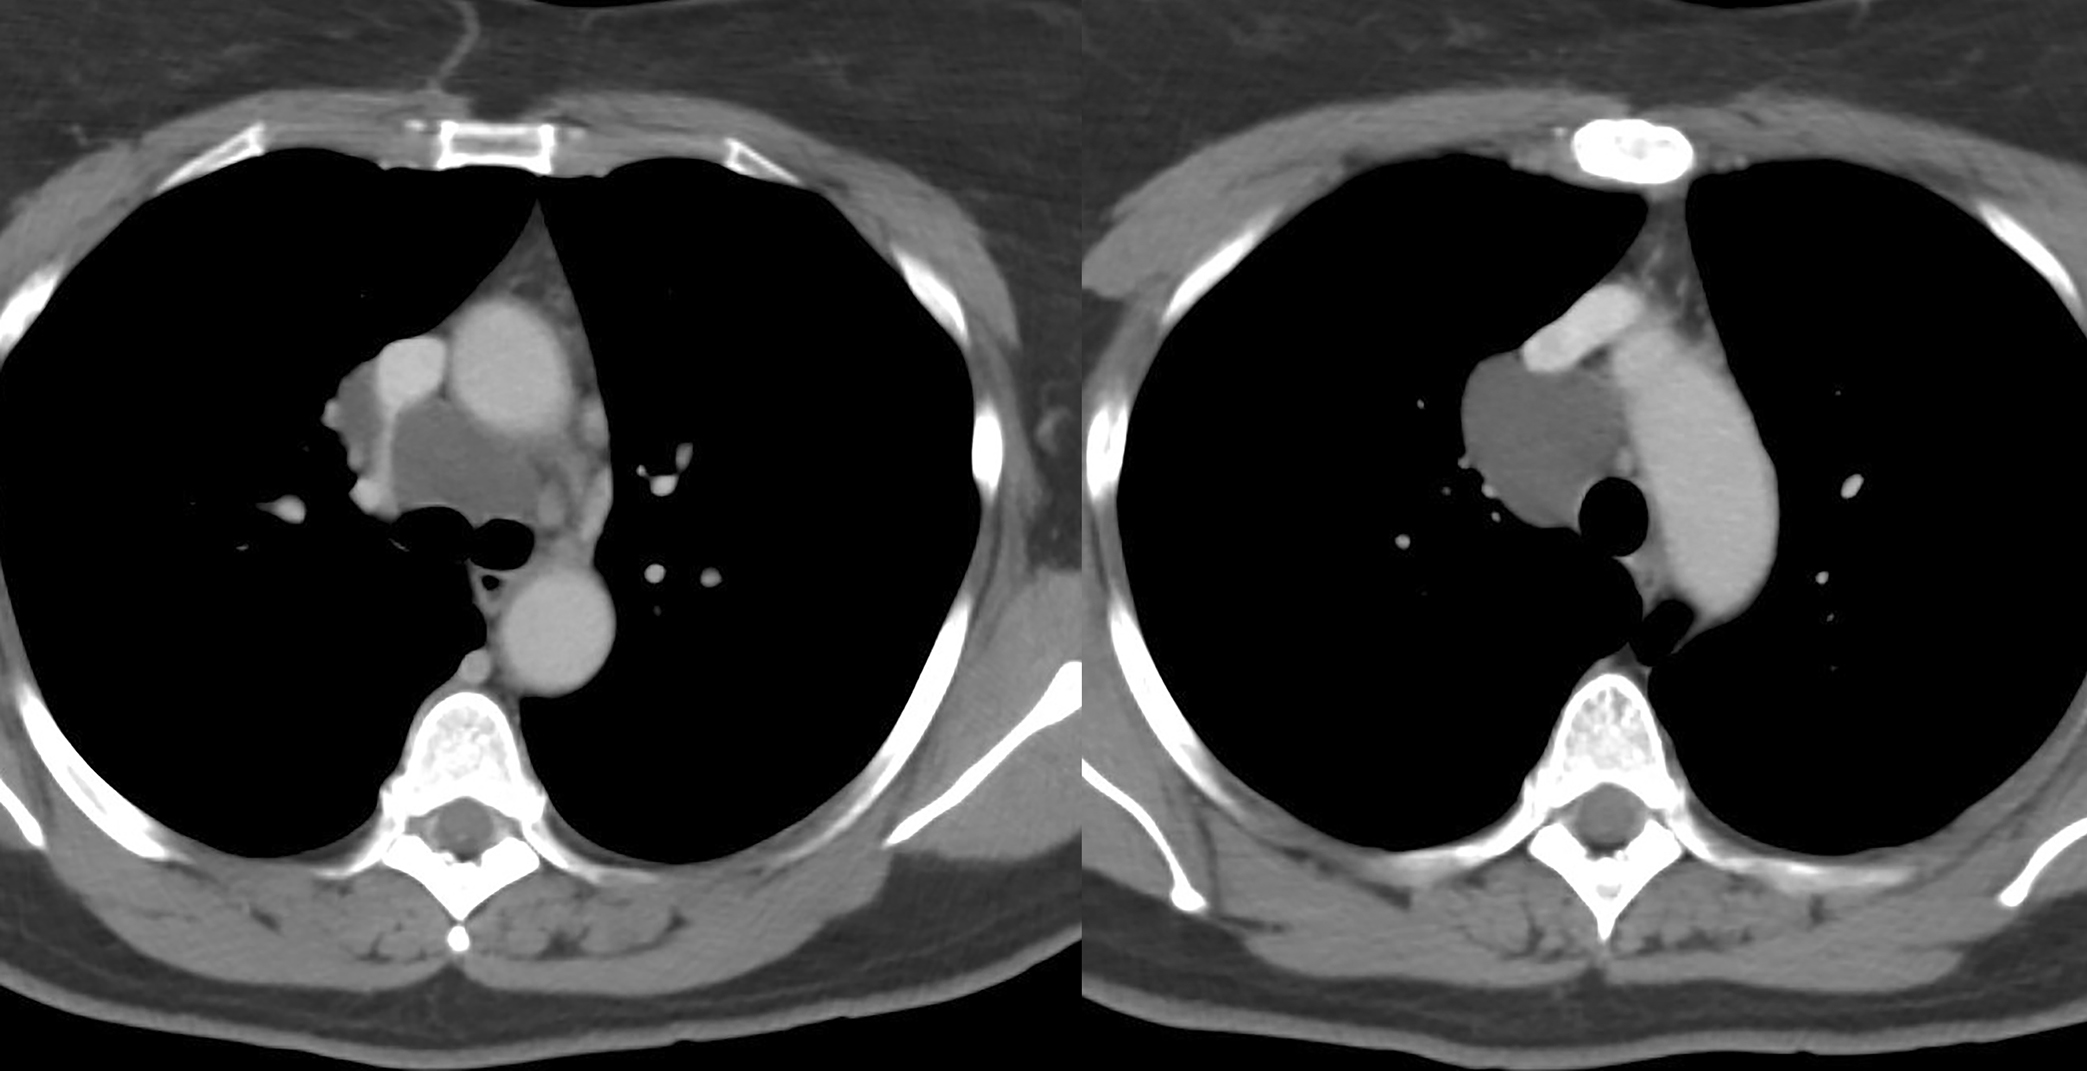

Bronchogenic cyst CT

Br Cyst CT